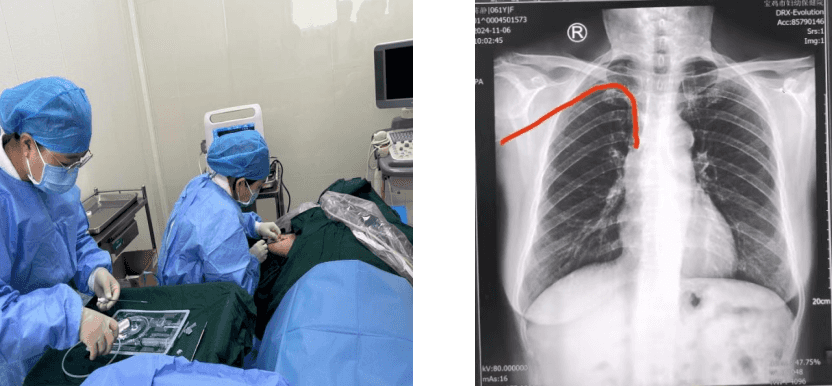

手术中,丁梅在超声影像辅助导引下,运用塞丁格技术,成功将导管沿张女士右臂贵要静脉送至预定位置附近,副主任护师王敏娟通过腔内心电图(ECG)定位技术实时监测,将导管尖端送达上腔静脉与右心房交界处,主治医师罗欢在穿刺点下进行囊袋制作,连接好导管与港座,进行了港体埋置和缝合,术后X线检查确定输液港导管末端位置良好,手术用时仅有30分钟,整个过程非常顺利,张女士全程无任何不适。